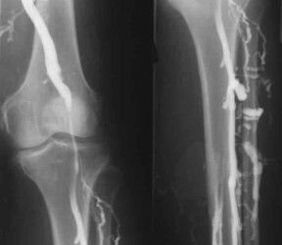

The most common instrumental diagnostic method is the use of ultrasound examination of the venous vessels of the legs.This technique allows you to visualize the vascular system and identify the degree of advancement of the pathological process.

- Phlebography.